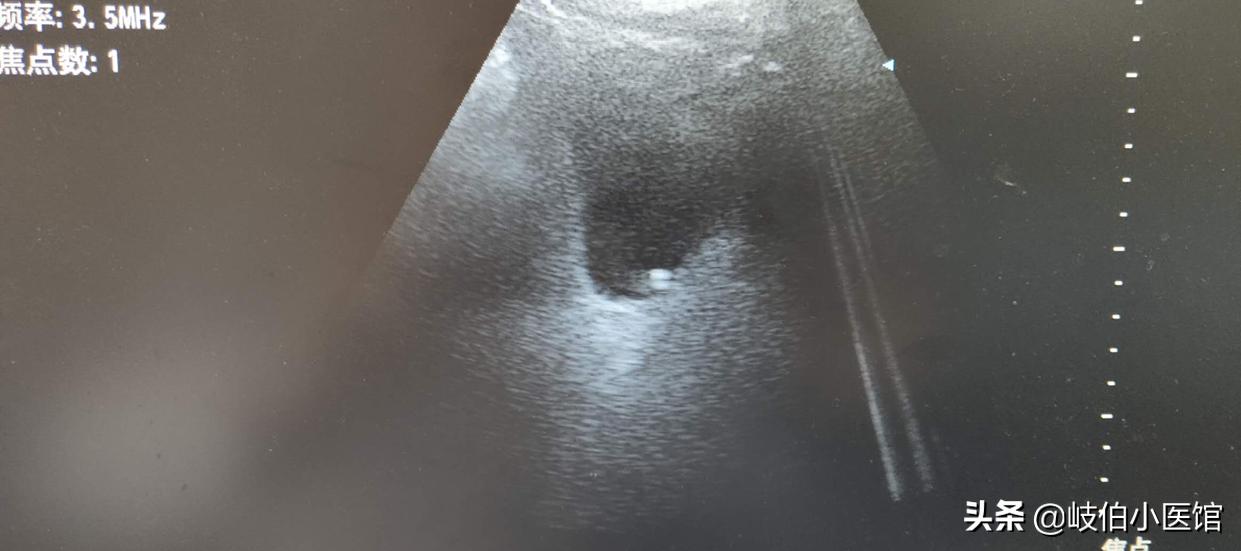

体外碎石术是现在临床上使用较多的治疗方法,是以冲击波发生器产生的冲击波,结石局部发生的一系列物理学效应(应力效应、裂解效应、空化效应、挤压效应)将结石粉碎。粉碎的结石随尿液排出体外。体外碎石有着效果好,患者痛苦少,安全有效,且费用低。

1.肾结石:直径小于或等于2cm的肾单发结石是体外碎石的最佳适应症。直径大于2cm的结石体外碎石作为可选方案,但术前需放置输尿管支架管,防止形成石街。

2.输尿管结石:输尿管结石各段均可用体外碎石治疗。长径小于或等于1.5cm的中、上段输尿管结石是体外碎石的最佳适应症。